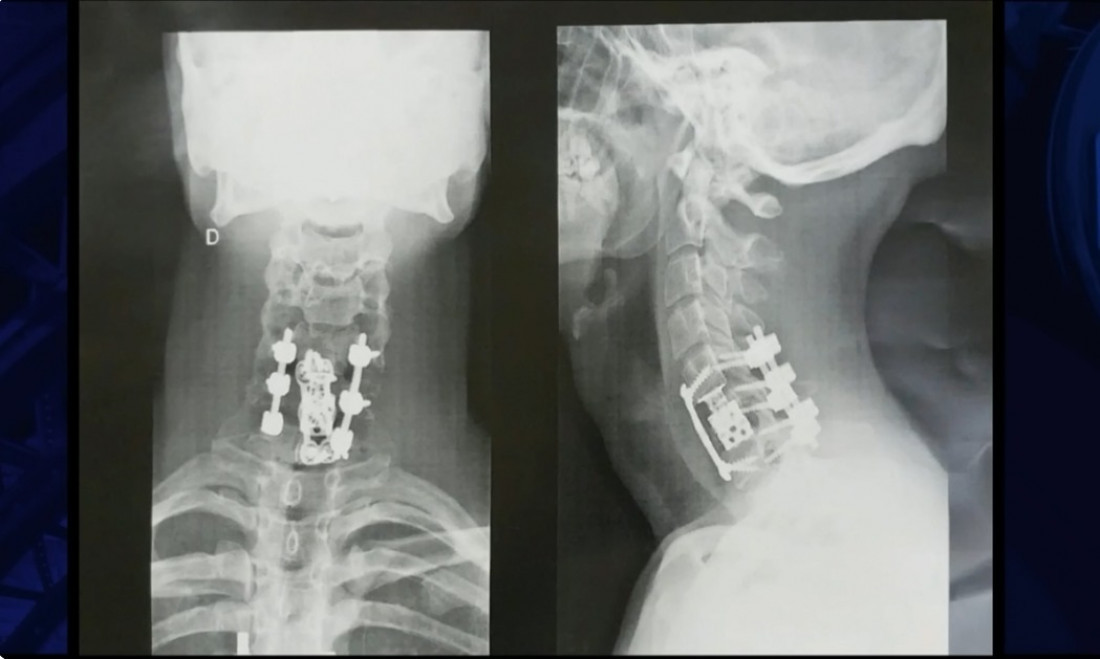

Mas o caso mais incrível é o de Bruno Drummond de Freitas, de 31 anos, diagnosticado com tetraplegia após um acidente automobilístico. Bruno recuperou completamente os movimentos depois de receber a aplicação da polilaminina. O caso de Bruno era bastante grave, pois ele fraturou a vértebra C6 em uma região muito próxima ao pescoço, o que tornava a recuperação impossível.

A radiografia após a cirurgia e o início do processo de recuperação de Bruno

• A radiografia após a cirurgia e o início do processo de recuperação de Bruno (Fotos: DIVULGAÇÃO_THE NOITE SBT)

Logo após dar entrada no hospital, ele foi levado para a mesa de cirurgia para a implantação de um pino na coluna fraturada — um procedimento ortopédico que, por si só, não devolveria os movimentos, já que a medula fica dentro do osso da coluna. Enquanto os médicos preparavam a cirurgia, um membro da equipe comentou sobre o medicamento desenvolvido pela equipe da Dra. Tatiana. Um tio de Bruno, que é médico, fez uma rápida pesquisa na internet e consultou outra pessoa da família, uma médica neurocirurgiã, que já conhecia o estudo e disse que valia a tentativa, já que o quadro era considerado irreversível. “Pior do que eu estava, não poderia ficar”, contou Bruno em entrevista ao jornalista Danilo Gentili, no programa “The Noite” (SBT).